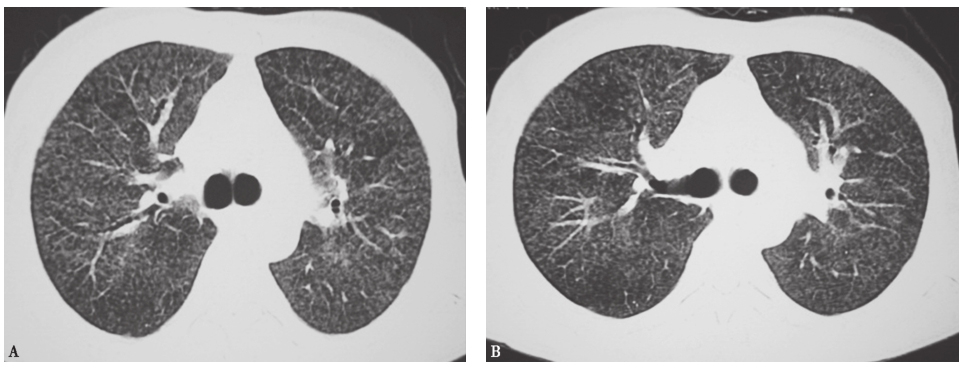

患者经泼尼松(20mg,每天2次)口服治疗,并且脱离原有工作环境,1个月后复查胸部HRCT示两肺磨玻璃影及小结节影较前进一步吸收(图17),咳嗽、气喘症状明显缓解。

图17泼尼松治疗1个月后胸部HRCT表现

HRCT显示磨玻璃影及小结节影进一步减少,双肺胸膜下少量小结节影